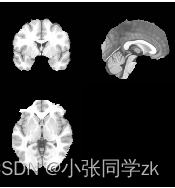

对ICBM152(脑成像国际联盟(International Consortium for Brain Mapping)所提供的标准空间模板)进行颅骨剥离的结果如图2.8.28所示:

图2.8.28 颅骨剥离